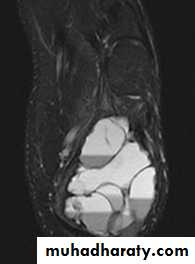

CT scans and MRI will reveal the extent of the tumour, both within the bone and beyond.

show a radiolucent area situated eccentrically at the end of a long bone and bounded by the sub- chondral bone plate.

The endosteal margin may be quite obvious, but in aggressive lesions it is ill-defined.

The Centre sometimes has a soap-bubble appearance.

The cortex is thin and sometimes ballooned. aggressive lesions extend into the soft tissue.43

The appearance of a ‘cystic’ lesion in mature bone, extending right up to the subchondral plate, is so characteristic